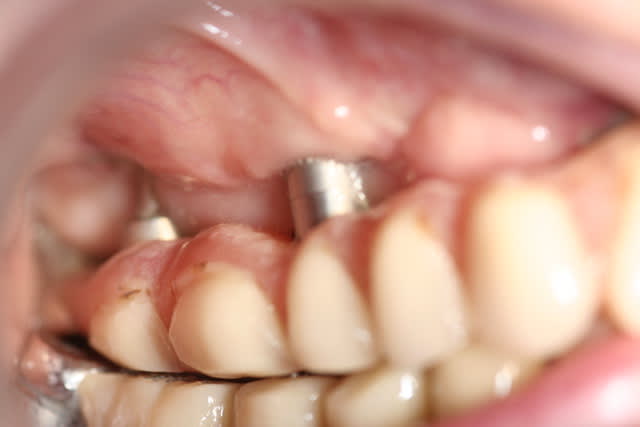

ça aussi c'est fait par le grand Maître, je garderai mon avis pour moi parce que je n'ai pas compris le rationnel pour faire ça à une patiente...

C'est quand même d'un point de vue technique sacrément impressionant...

oui mais autour de cette radio il y a une patiente qui doit vivre, maintenir et avoir mal après cette prouesse technique. je préfère un truc simple qui marche à une prouesse technique qui merde